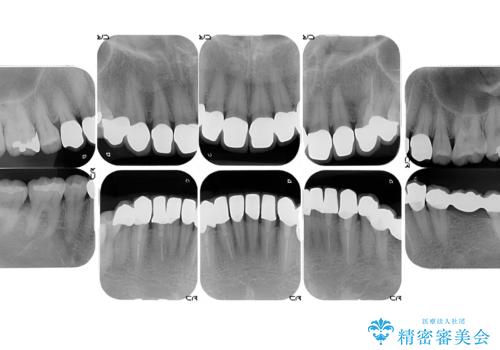

- 前歯の色や形を全体的に綺麗したいといらっしゃった方の症例です。

上顎は左側 4 番目から右側 4 番目までの 8 歯をオールセラミッククラウンで補綴しました。

下顎は左側 4 番目から右側 4 番目までの 8 歯と左下 567 ブリッジをオールセラミッククラウンで補綴し、右下67の銀歯はセラミックインレーによる修復を行いました。